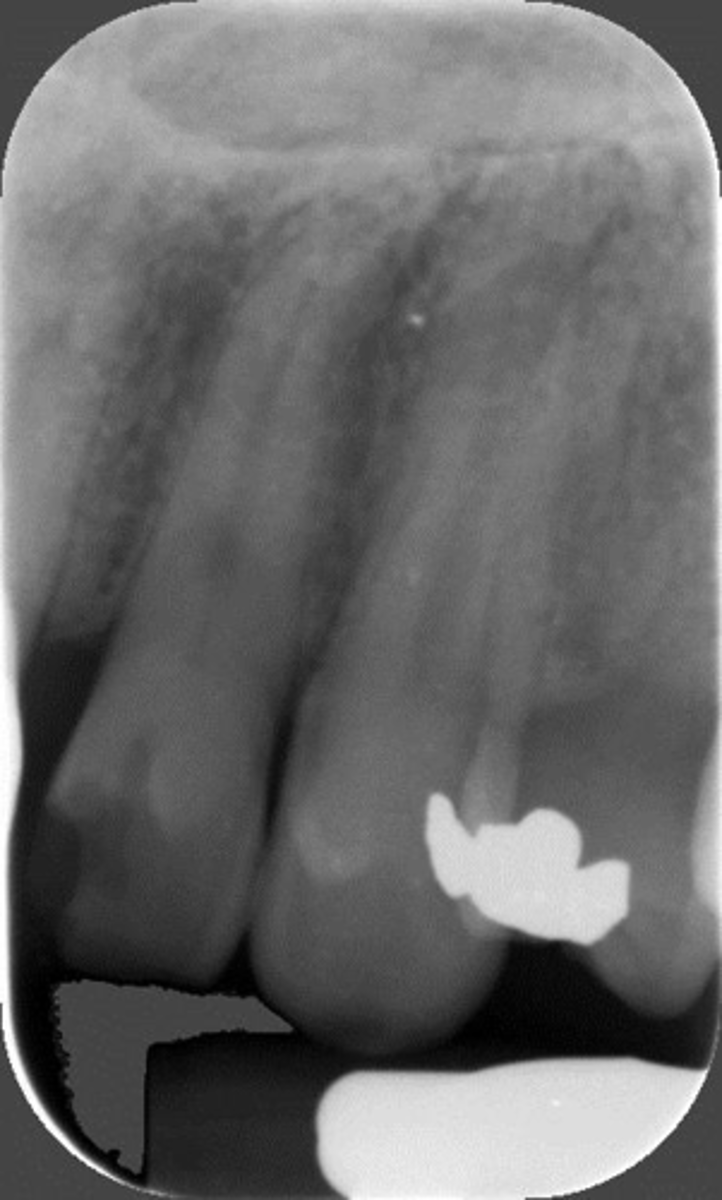

Elongated, vertical angulation, film holder (metal bar)

What is this error?

Damage, elongation, can't see apices

Rinn instrument bar, vertical angulation